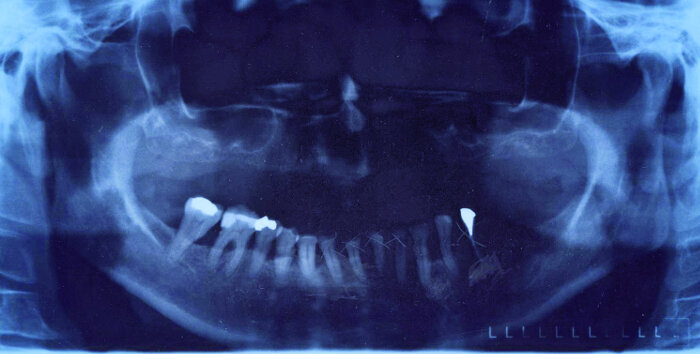

Si l’on a bien conscience de ce fait, on s’aperçoit qu’on le rencontre très couramment. L’inverse (une influence plus forte du père) touche une minorité de gens (Fig. 7). Un alignement parfait des deux incisives témoigne d’une influence équilibrée des deux parents. Un exemple de situation réelle : la Figure 8 montre deux incisives centrales fracturées (dents 11 et 21) dont la gauche a finalement été extraite en raison d’une fracture radiculaire. Les parents de la patiente avaient divorcé. Le juge l’avait placée sous la garde du père et avait confié l’autre enfant à la mère. La patiente avait ainsi perdu sa mère et symboliquement sa dent 21.

J’observe habituellement des diastèmes (Fig. 9) chez des patients dont les parents semblent vivre ensemble mais finalement mènent chacun leur vie. Les patients présentant des diastèmes connaissent généralement des relations difficiles avec un partenaire. Bien sûr, ce ne sont généralement pas les personnes concernées qui vous fournissent de telles informations. Ces recoins secrets des ménages, on les découvre si l’on est le dentiste de famille depuis de nombreuses années.